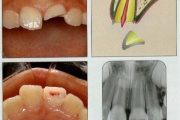

Hambatraumad

Põhimõtted – Trauma tagajärjel irdunud jäävhammast tasub alati tagasi istutada, kui õnnetuses on hammas ja alveool terveks jäänud. Kui ka hammas hiljem kaotataks, on istutamine tähtis, sest see kergendab implanteerimist ja lükkab edasi hamba asendamist proteesiga. – Mingil juhul ei Loe edasi »